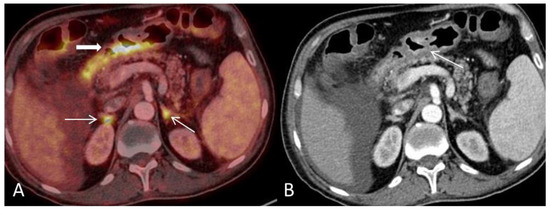

(A) Axial PET and CT fused image shows pathological high FDG-uptake in the large-bowel in two different patterns corresponding to the lumen (arrow) and in the outer wall (bold arrow) respectively and is consistent with an inflammatory response. (B) CT scan shows mural stratification (i.e., visualization of two or three different layers of the bowel wall) of the thickened large-bowel wall (defined as >3 mm) with mucosal (arrowhead) and serosal enhancement (arrow). The PET/CT findings described here are typical for acute GVHD-GIT or inflammatory bowel disease. Ascites is a common finding in acute-GVHD and has been reported to occur in 45% of affected patients (bold arrow) [2].